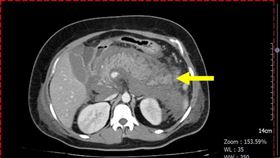

33歲陳先生號稱酒國英雄,日前與友人徹夜豪飲,返家後...